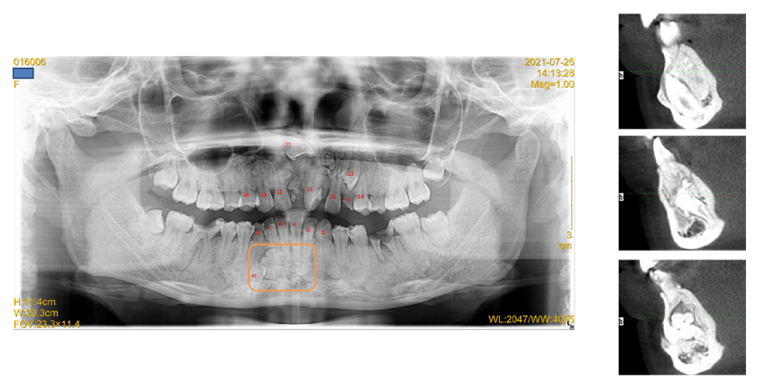

从牙片上看,她的牙齿简直“乱成了一锅粥”:

在上下颌骨上,除了正常的牙齿以外,还长了30多颗形态各异的“类牙样物质”;

右侧的门牙完全阻生,长在鼻子底下,一颗米粒大的多生牙“鸠占鹊巢”,占了原本门牙的位置;

由于无法咬合,和右侧门牙对应的下中切牙异常伸长,牙齿整体的咬合关系非常差;

多颗牙齿发生龋齿,其中一颗磨牙龋坏只剩下残根;

还有一颗侧切牙,其实是一颗滞留的乳牙;

此外,还发现一个2cm*1.5cm大小的混合型牙瘤,和正常牙齿根尖粘连,未来可能发生病变形成囊肿,导致骨质强度降低,甚至可能引起颌骨骨折、掉牙。

经正畸科和口腔颌面外科会诊,由于患者的多生牙数量非常多,骨密度病理性异常升高,呈现骨质不均匀、硬、脆等特点,矫治效果无法预期,失败率高,需要先拔除多余的牙齿。考虑到符合手术指征,而且杨女士想要拔除多生牙的意愿强烈,于是决定进行手术拔除。

一个多小时手术后,医生成功取出了35颗大小形态各异的牙齿、残根或类牙样物质。目前,杨女士术后恢复良好,等待择时矫治。